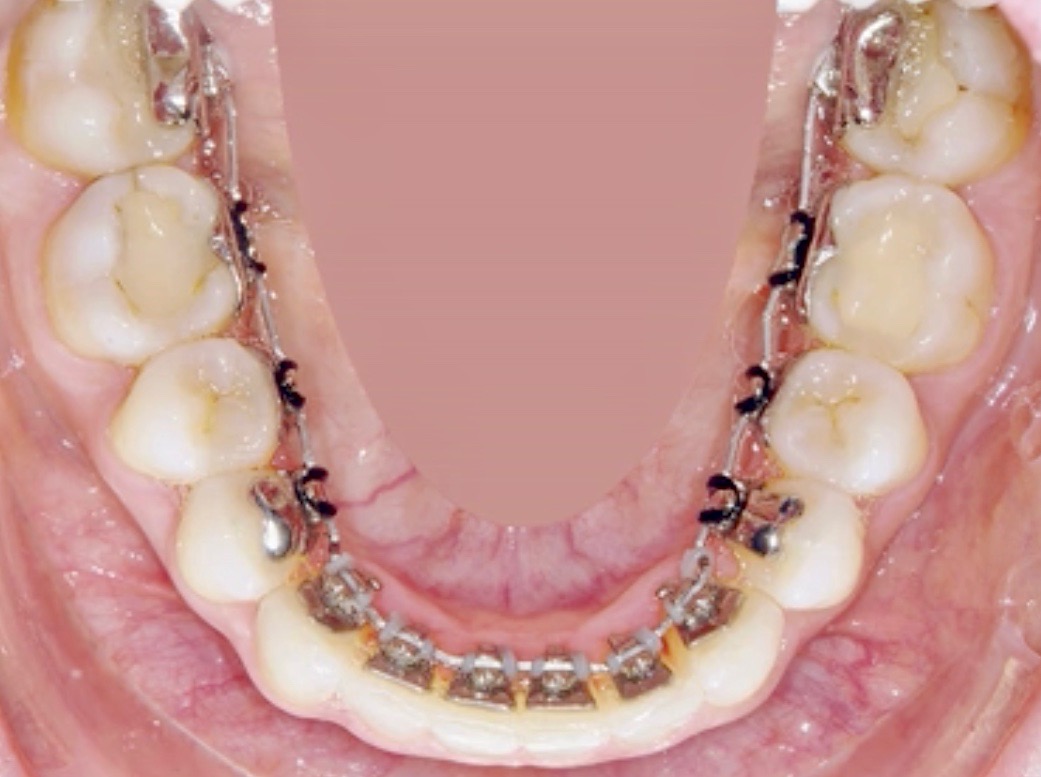

Le piastrine ortodontiche (brackets) vengono applicate sul lato linguale dei denti e non più sul lato esterno. In questo modo il trattamento ortodontico sarà completamente invisibile!

Le piastrine sono costruite ad hoc, fatte ognuna per il dente specifico sul quale viene attaccata. I fili sono piegati da sofisticati robot a controllano numerico, così i movimenti dentali sono controllati grazie al controllo tecnologico che contraddistingue questo trattamento!